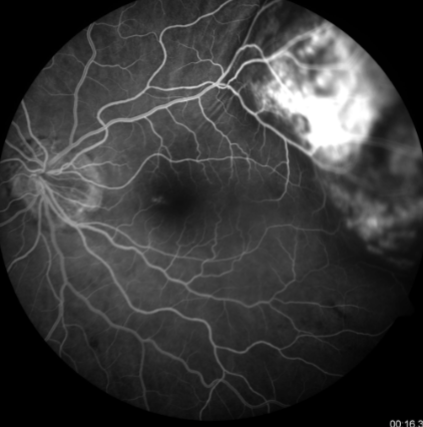

mottled fluorescence in arteriovenous phase, progressive staining, prolonged dye retention, double circulation

what does a choroidal melanoma show on IVFA?

choroidal melanoma

melanoma

melanoma

melanoma

melanoma

melanoma

melanoma

melanoma

melanoma

melanoma

melanoma

melanoma

melanoma

melanoma

melanoma

melanoma

melanoma